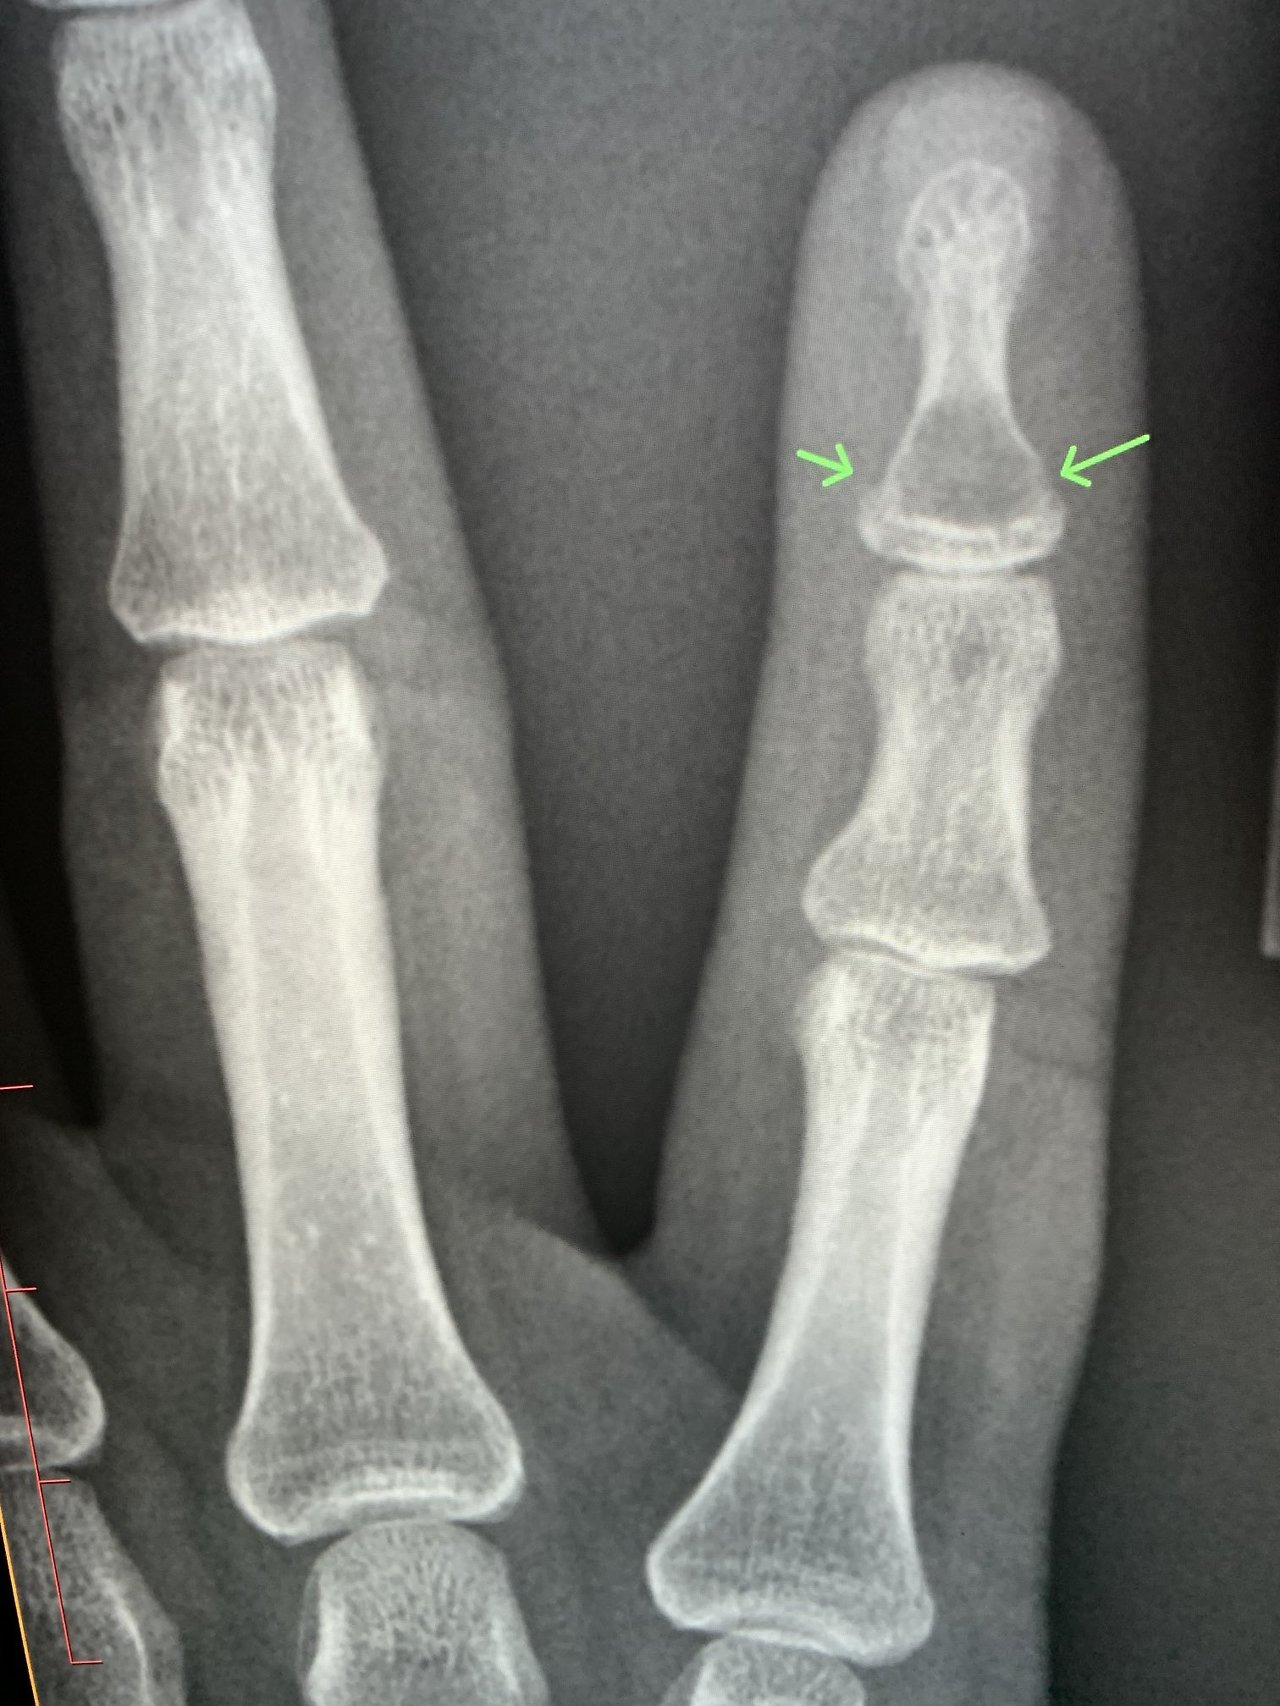

진료비와 검사비

- X-ray 촬영: 기본적으로 뼈 상태를 확인하기 위해 X-ray 촬영이 이루어지며, 병원에 따라 2~5만 원 내외의 비용이 들 수 있습니다.